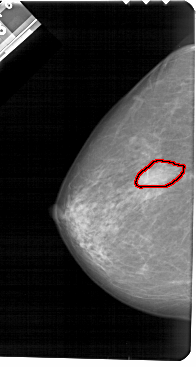

A_1483_1.LEFT_MLO

LEFT_MLO LINES 5491 PIXELS_PER_LINE 3196 BITS_PER_PIXEL 12 RESOLUTION 43.5 OVERLAY

FILE: A_1483_1.LEFT_MLO.OVERLAY

TOTAL_ABNORMALITIES 1

ABNORMALITY 1

LESION_TYPE MASS SHAPE IRREGULAR MARGINS ILL_DEFINED

ASSESSMENT 4

SUBTLETY 5

PATHOLOGY BENIGN

TOTAL_OUTLINES 1

BOUNDARY